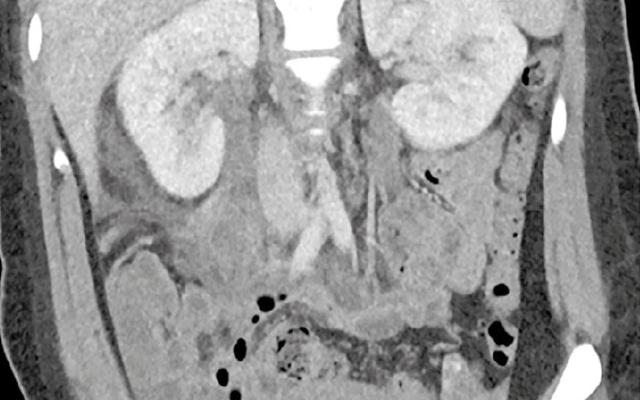

Een 59-jarige vrouw kwam op de Spoedeisende Hulp vanwege pijn rechtsonder in de buik sinds 4 dagen. Zij had drukpijn ter plaatse van het punt van McBurney en een CRP-waarde van 43 mg/l (referentiewaarde: < 4). Een echo liet een cilindrisch aanhangsel van het caecum zien, met een diameter van 18,3 mm. Omdat wij een slagschaduw zagen, met zichtbare wandlagen, een spoortje vrij vocht en induratie van het omliggende vetweefsel, werd het beeld geduid als appendicitis acuta met fecoliet (figuur 1a). Tijdens laparoscopie bleek sprake van een appendix sana (figuur 2) en een ongecompliceerde ontsteking van een caecumdivertikel (figuur…